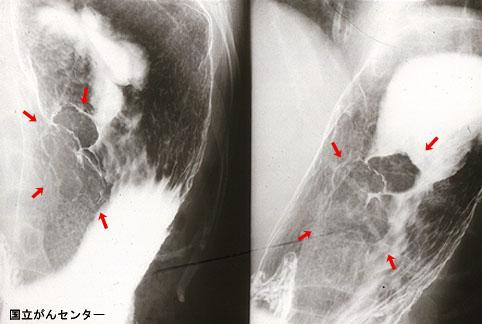

疾病(病理主体)的分类恶性上皮性肿瘤/腺癌

部位(按器官分)胃(部位)/体部

检查方法X线

肿瘤的肉眼分类0型(表在型)/I型(I)

肿瘤最大直径40以上

肿瘤的深度sm